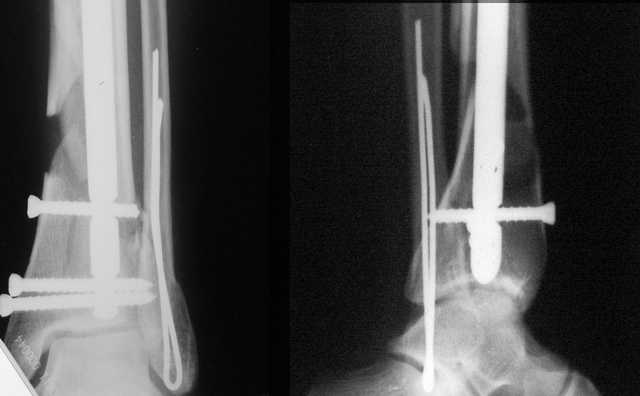

АЧ>Какие тут аргументы в пользу выбора пластины, а не интрамедуллярного гвоздя?

Классически показанием для locked nail яв-ся зоны BC CD, до появления LCP показания к locked nail несколько расширялись в зоны AB и DE

Аргументы: перелом достаточно низкий, трудно будет ввести 3-и блок. винта, а учитывая характер перелома на 2-х дистальных винтах я бы не рекомендовал немедленную полную нагрузку.

С Уважением А.Миронов

Кликните для загрузки файла DSC00841.JPG

АМ> Аргументы: перелом достаточно низкий, трудно будет ввести 3-и блок.

АМ> винта, а учитывая характер перелома на 2-х дистальных винтах я бы не

АМ> рекомендовал немедленную полную нагрузку.

Положим, и с 2 винтами она к 2 месяцам была бы тут вполне реальна. Кроме того, есть возможность ввести винты мимо гвоздя (Poller), и таки разрешить раннюю полную нагрузку (что еще зависит от массы тела пациента и диаметра винтов). А уж если сопоставить стоимость отечественного гвоздика и пластины Synthes... Если бы на порядок более дорогая железка давала на тот же порядок лучший результат... ;-)